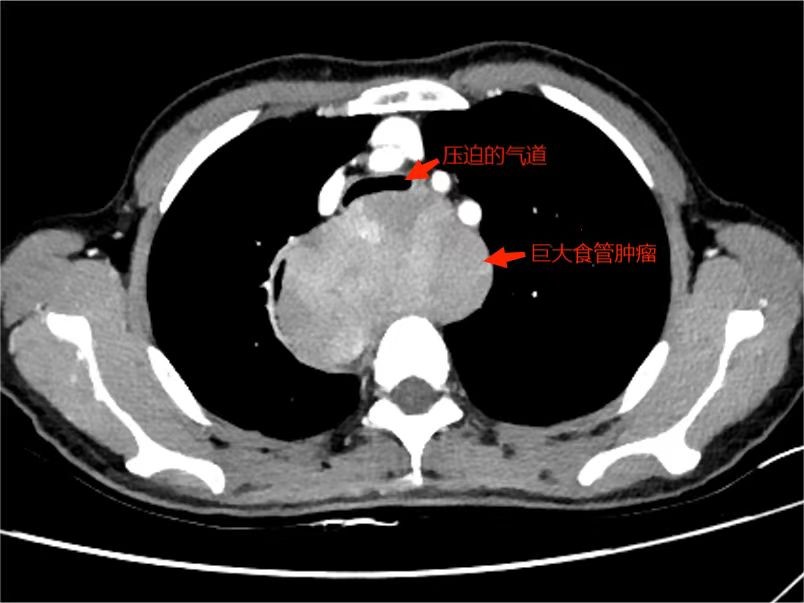

熊荣生主任在仔细研究金阿姨的病情和检查结果后,考虑到食管肿瘤大(10.2cm×8.2cm×5.8cm)压迫气道引起气道狭窄。若继续保守治疗,随着肿瘤的继续增大,呼吸及吞咽困难的症状将会持续加重。若考虑进行手术切除,可能出现麻醉时通气困难、麻醉后气管软化塌陷,造成窒息缺氧危及生命。

影像图